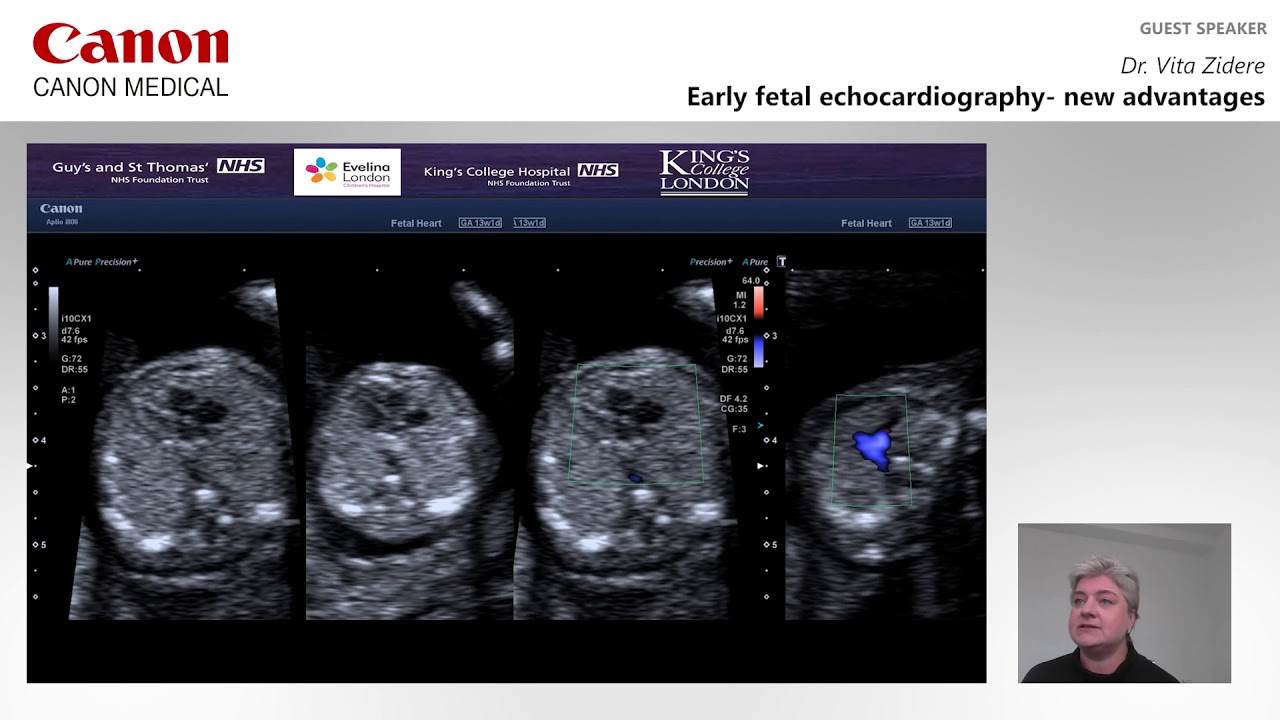

Presented at ISUOG 2020, Dr. Vita Zidere from the United Kingdom discusses the latest advantages of the ultrasound imaging in fetal echocardiography.